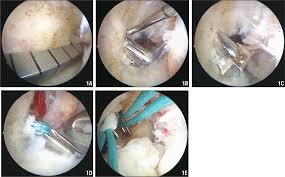

Έτσι στο Ιασώ τα τελευταία 2 χρόνια χρησιμοποιώ και έχω εξελίξει μαζί με την ομάδα μου την τεχνική all insight technique for ACL reconstruction.

Σε σχέση με τις παλαιότερες τεχνικές χρειάζεται η λήψη μόνο ενός μοσχεύματος (του ημιτενοντώδη) και όχι δύο που γινόταν μέχρι πρότινος. Η παρασκευή του γίνεται με ειδικό τρόπο

και η τοποθέτηση αυτού γίνεται μέσα από την άρθρωση του γόνατος όπου με ειδικά εργαλεία δημιουργούνται τούνελ στο μηρό και στη κνήμη από μέσα από την άρθρωση προς τα έξω.

Άρα τα τούνελ είναι πλέον μικρότερα σε μήκος από τις σύνηθες τεχνικές με αποτέλεσμα να μην πειράζουμε το έξω τμήμα του οστού (corticalis), η απώλεια οστού είναι αρκετά λιγότερη και τα μαλακά μόρια προφυλάσσονται στο μέγιστο.